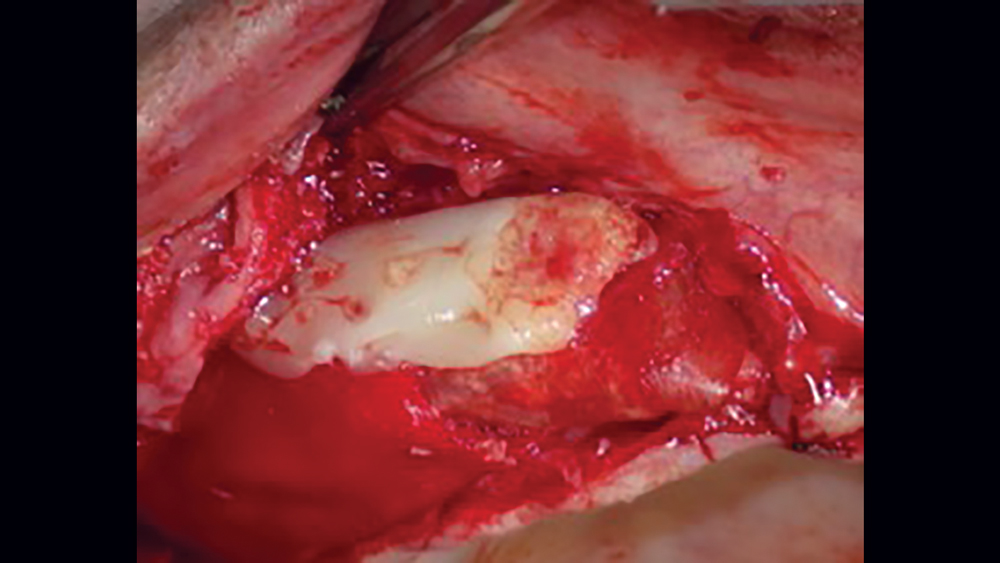

Acellular Dermal Matrix

Acellular dermal matrix (ADM) is a biocompatible human (allograft) connective-tissue matrix derived through a process of removing all cells within the dermis. Because of the cells being removed during the manufacturing process, no viruses may be transmitted. Additionally, because of the acellular nature of this membrane, no inflammatory reactions or rejection will occur. The inert allograft, when used as a membrane, acts as an architectural framework that allows for fibroblast migration and vascularization (Figs. 11a, 11b).

Figure 11a Acellular dermal matrix

Figure 11b acellular dermal matrix is applied to site

Figures 11a, 11b: Acellular dermal matrix is an inert allograft that may be used as a barrier membrane.